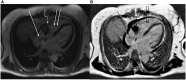

Figure 2

Baseline cardiac magnetic resonance imaging of the patient from January 2020.